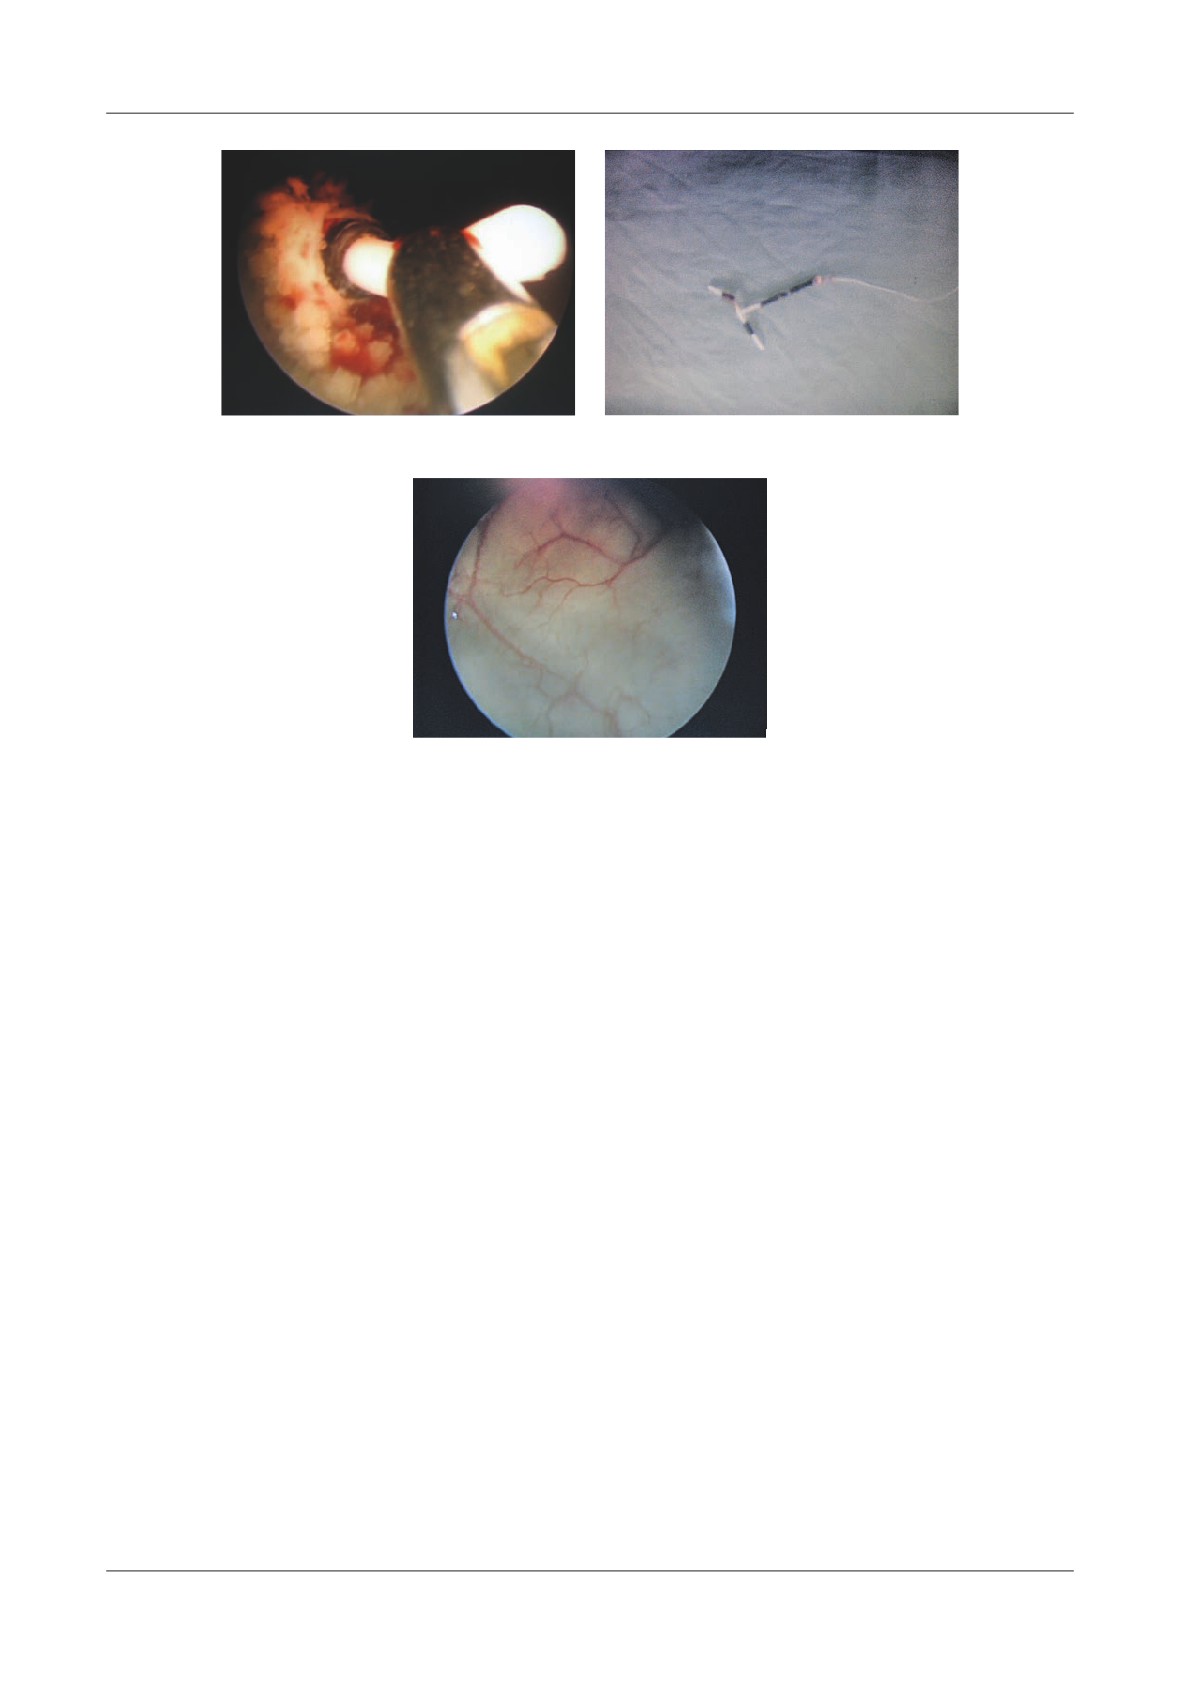

Figure 2. Infected pancreatic necrosis, more of 50% of the

onset (Fig. 2).

CT image is necrosis, with encapsulated liquefaction

According to our experience the detection of gas in

and air bubbles

the necrotic tissue was present in 12% of cases (Figure

2). Such CT  ndings are indicative of infected necrosis.

Figure 3. Pancreatic abscess. 5 weeks following acute

65%.

pancreatitis, heterogeneous  uid collection anterior to the

Cysts >6cm in diameter required surgical treatment

body and tail of the pancreas. Pancreatic ducts are distended

Figure 4. Pancreatic pseudocyst secondary to necrosis.

A - Liquefaction necrosis in the tail, B - Large pseudocyst bulging into the stomach

Figure 5. Pseudocyst communicating with  the pancreatic duct, A-With CT image of enlarged gland

and peripancreatitis, B-After discharge from hospital, 2 weeks later, CT shows a residual collection,

C-6 months later, the patient had abdominal pain, CT shows an enlarging pseudocyst,

D-Trans gastric punction with  stulography, shows communication with the Wirsung duct